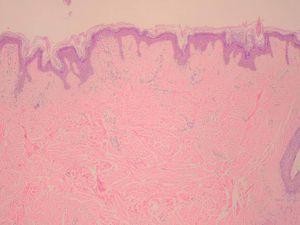

Una niña sana de 13 años acudió a nuestra consulta para valoración de una lesión cutánea congénita en la espalda. En el momento de nacer, la niña había presentado una lesión apenas perceptible en la zona afectada, pero, con el paso de los años, ésta había engrosado notablemente. Ningún miembro de la familia refería patología cutánea similar, ni la paciente presentaba lesiones semejantes en otras partes del cuerpo. No existían antecedentes familiares de interés, y el desarrollo psicomotor de la niña era normal. En la exploración física se apreciaba una extensa lesión cutánea pigmentada en la región lumbar de la espalda, de aproximadamente 20 cm de diámetro, superficie cerebriforme, consistencia firme y límites mal definidos (fig. 1). El estudio histológico demostró un aumento del espesor dérmico a expensas de una dermis reticular ensanchada y ocupada por gruesas bandas de colágeno irregularmente dispuestas (fig. 2). La tinción con orceína demostró una clara disminución de fibras elásticas en la dermis reticular. La exploración neurológica, el ecocardiograma y la tomografía axial computarizada (TAC) craneal fueron normales. Con el diagnóstico de colagenoma cerebriforme solitario gigante, se valoró tratamiento quirúrgico de la lesión, descartándose el mismo dada la ausencia de sintomatología y las inevitables secuelas cicatriciales.

Fig. 2.--El estudio histológico con hematoxilina-eosina puso de manifiesto una acantosis irregular con elongación de la red de crestas e hiperquertosis ortoqueratósica en la epidermis. La dermis papilar estaba homogeneizada, y anchas fibras colágenas de disposición irregular ocupaban la dermis reticular. (HE, x10.)